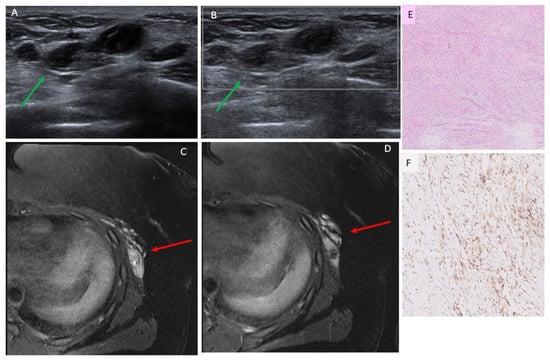

| 5 | 3.4 | Ultrasound core needle biopsy | N/a | Irregular, parallel, hypoechoic masses with indistinct/angular margins, posterior acoustic enhancement and no Doppler flow | Suspicious, 4A–4B | Lobulated mass with irregular margins and heterogeneous enhancement |

| 9 | 2.5 | Ultrasound core needle biopsy | N/a | Oval, parallel, heterogeneous mass with indistinct margins, posterior acoustic enhancement and Doppler flow | Suspicious, 4A–4B | Irregular mass with irregular margins and heterogeneous enhancement |